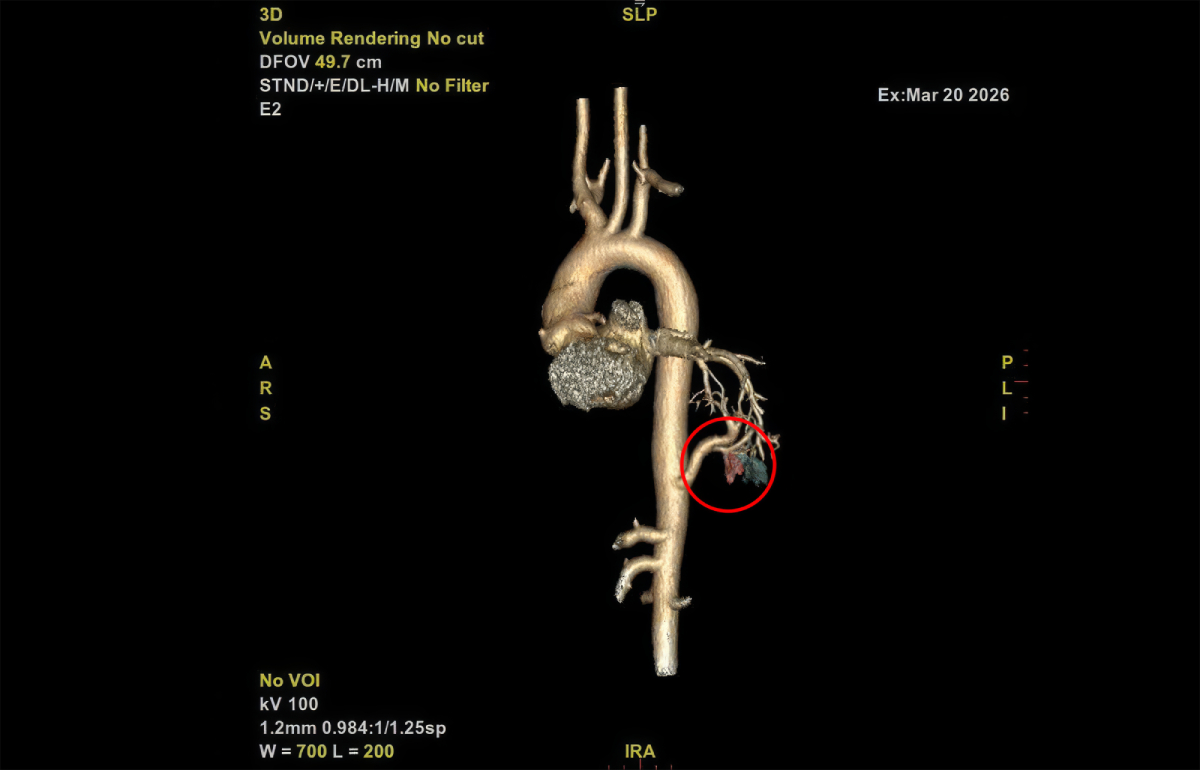

PGS.TS.BS Vũ Hữu Vĩnh, Giám đốc Trung tâm Ngoại Lồng ngực – Mạch máu, Bệnh viện Đa khoa Tâm Anh TP.HCM, cho biết kết quả chụp CT ghi nhận người bệnh có một nhánh động mạch bất thường từ động mạch chủ đến phổi trái, bác sĩ xác định người bệnh mắc dị tật phổi biệt trí (hay còn gọi là phổi biệt lập) nội thùy tại thùy dưới phổi trái. Đây là dị tật bẩm sinh ít gặp và khá nghiêm trọng, chiếm dưới 6% các dị tật phổi bẩm sinh.

Sau khi mở 3 lỗ khoảng 1 cm trên lồng ngực, dưới sự dẫn đường của hệ thống camera phóng đại, êkíp tiếp cận nhánh động mạch bất thường, khéo léo tách rời khỏi các tổ chức xung quanh, thực hiện thắt nút nhánh động mạch này để ngăn nguồn cấp máu. Khi dòng máu áp lực cao ngừng đổ vào, thùy phổi trái tổn thương dần xẹp xuống, bớt căng phồng. Lúc này, phó giáo sư Vĩnh mới tiến hành cắt phần thùy phổi bị xơ hóa, bảo tồn tối đa các vùng phổi lành lặn còn lại.